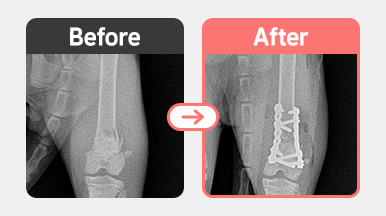

골절치료